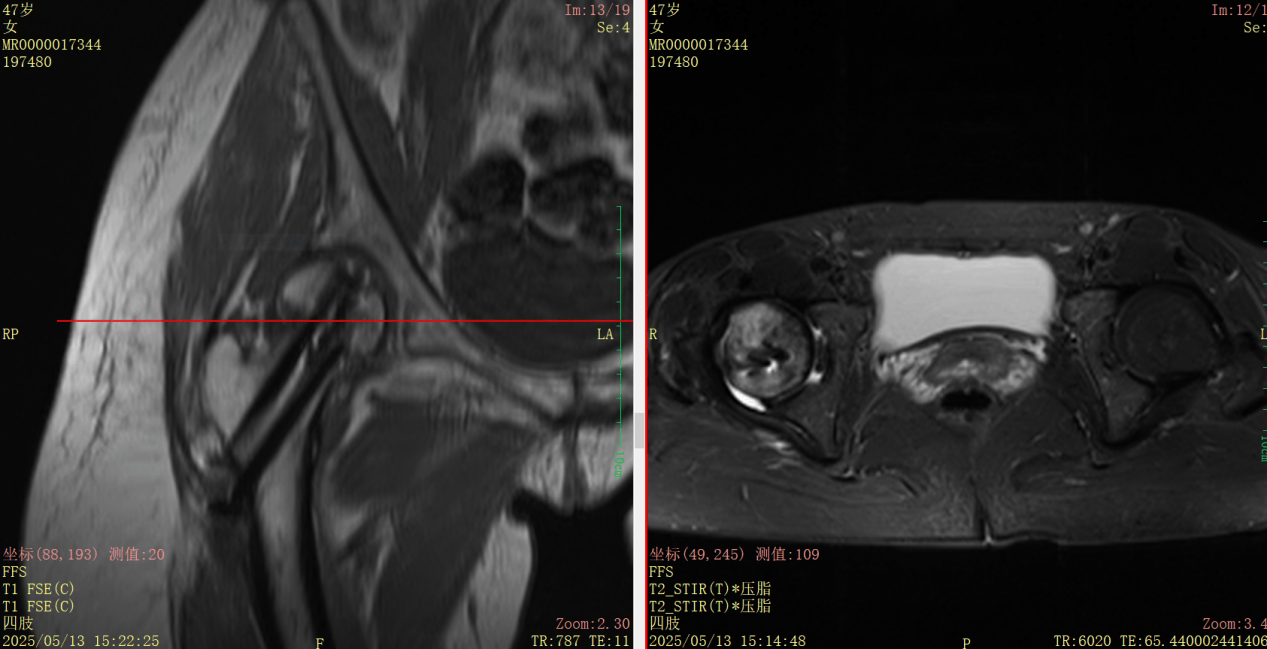

3. 动态监测护航: 术后康复并非终点。团队全程动态监测Garden指数,确保其稳定在安全解剖范围内。术后6周结合MRI(如T2WI信号)科学评估股骨头血供变化,为康复计划提供精准依据。

诊断结果冰冷而严峻:左侧股骨颈头下型骨折(Garden IV型),严重错位分离。这意味着高达40%以上的股骨头坏死风险,以及漫长的康复之路。

面对如此高风险、高难度的骨折(Garden IV型,严重错位),湖州邦尔骨科医院叶博士团队深知,传统的治疗方式难以满足患者快速康复、最大限度保髋的期望。他们迅速制定了以“Garden指数”为金标、数字化微创技术为核心的精准治疗方案。